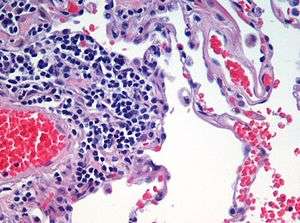

Haematoxylin and eosin (H&E) staining

Haematoxylin and eosin staining protocol is used frequently in histology to examine thin sections of tissue. Haematoxylin stains cell nuclei blue, while eosin stains cytoplasm, connective tissue and other extracellular substances pink or red. Eosin is strongly absorbed by red blood cells, colouring them bright red. In a skilfully made H & E preparation the red blood cells are almost orange, and collagen and cytoplasm (especially muscle) acquire different shades of pink. When the staining is done by a machine, the subtle differences in eosinophilia are often lost. Hematoxylin stains the cell nucleus and other acidic structures (such as RNA-rich portions of the cytoplasm and the matrix of hyaline cartilage) blue. In contrast, eosin stains the cytoplasm and collagen pink.